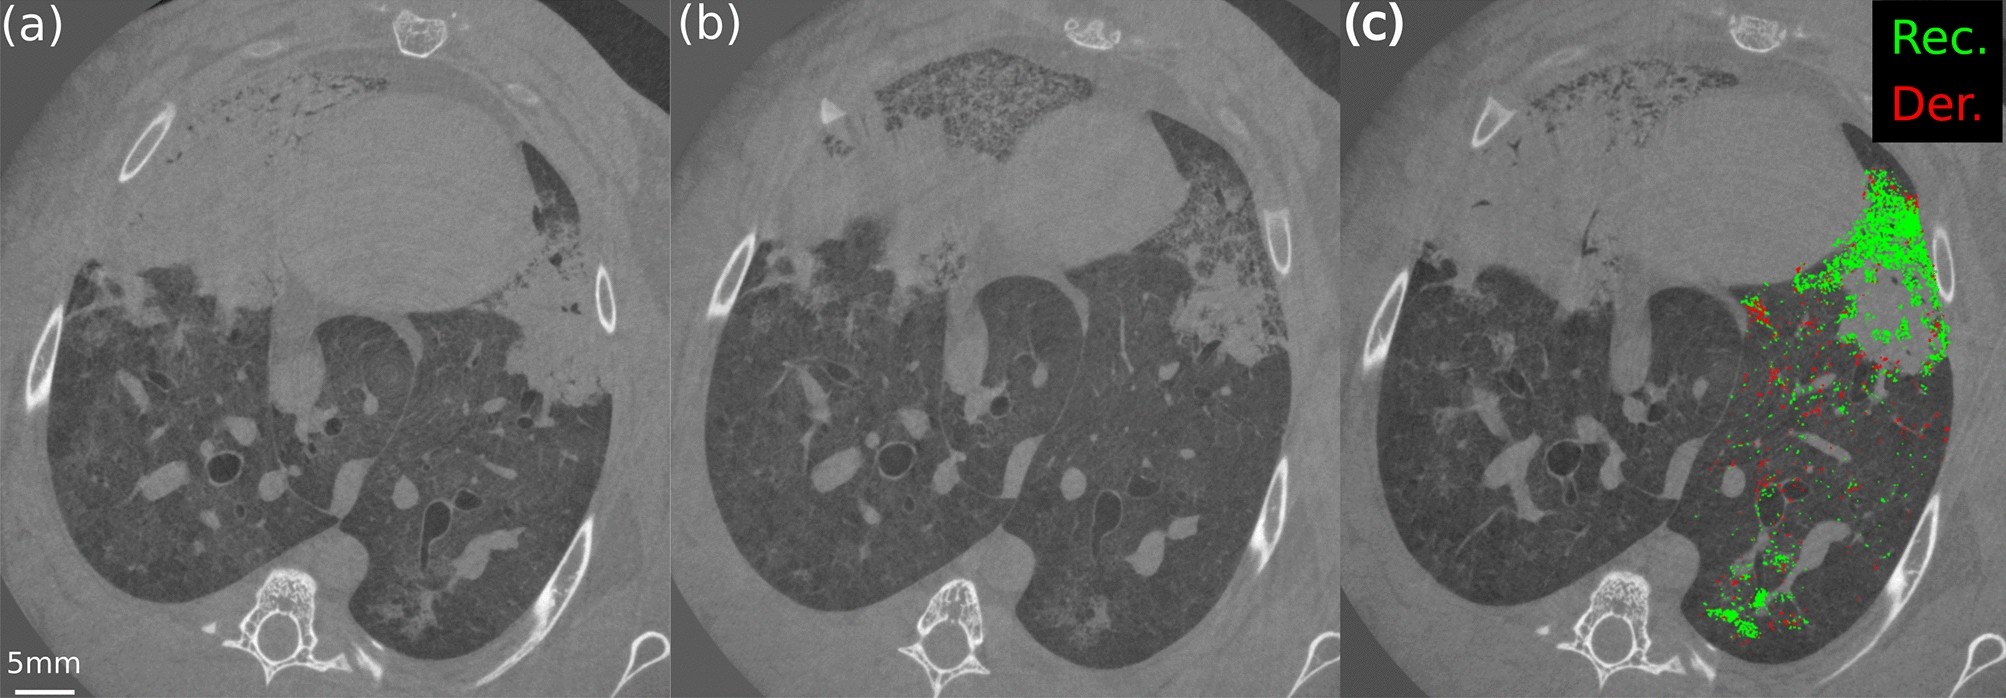

Figure 4

From: Imaging atelectrauma in Ventilator-Induced Lung Injury using 4D X-ray microscopy

In vivo dynamic CT of Rabbit-1 at minimum pressure at the beginning of inspiration (5 cmH2O) (a) and at maximum pressure at the end of the inspiration (25 cmH2O ) (b). In (c) a 2D projection of the recruitment (Rec., green) and derecruitment (Der., red) as identified by the algorithm in the left lung, superimposed to one CT slice as a reference. (c) represents the time instant, during the respiratory cycle, where maximum recruitment was observed.